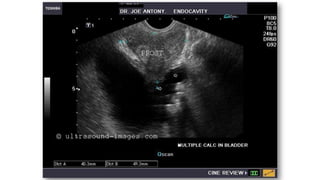

 Biopsia transrectal

guiada por

ultrasonido.

 Ultrasonografía

transrectal.